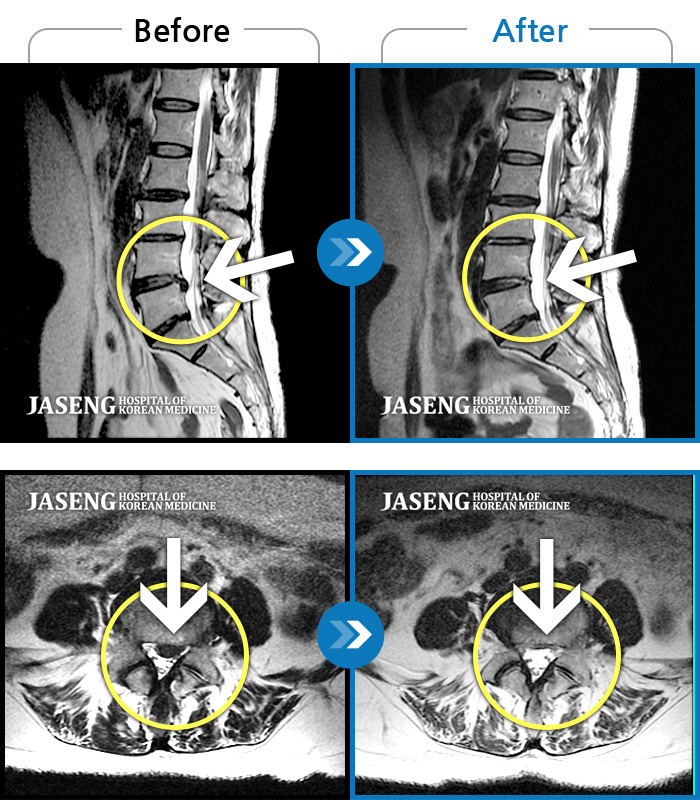

MRI사진에서 좋아지고 있다는 말씀에 넘 기뻤습니다^_^